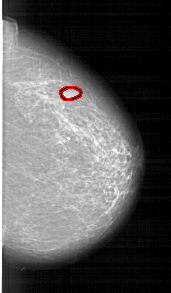

A_1261_1.LEFT_CC

LEFT_CC LINES 6661 PIXELS_PER_LINE 3601 BITS_PER_PIXEL 12 RESOLUTION 43.5 OVERLAY

FILE: A_1261_1.LEFT_CC.OVERLAY

TOTAL_ABNORMALITIES 1

ABNORMALITY 1

LESION_TYPE CALCIFICATION TYPE PLEOMORPHIC DISTRIBUTION CLUSTERED

ASSESSMENT 4

SUBTLETY 4

PATHOLOGY MALIGNANT

TOTAL_OUTLINES 1

BOUNDARY